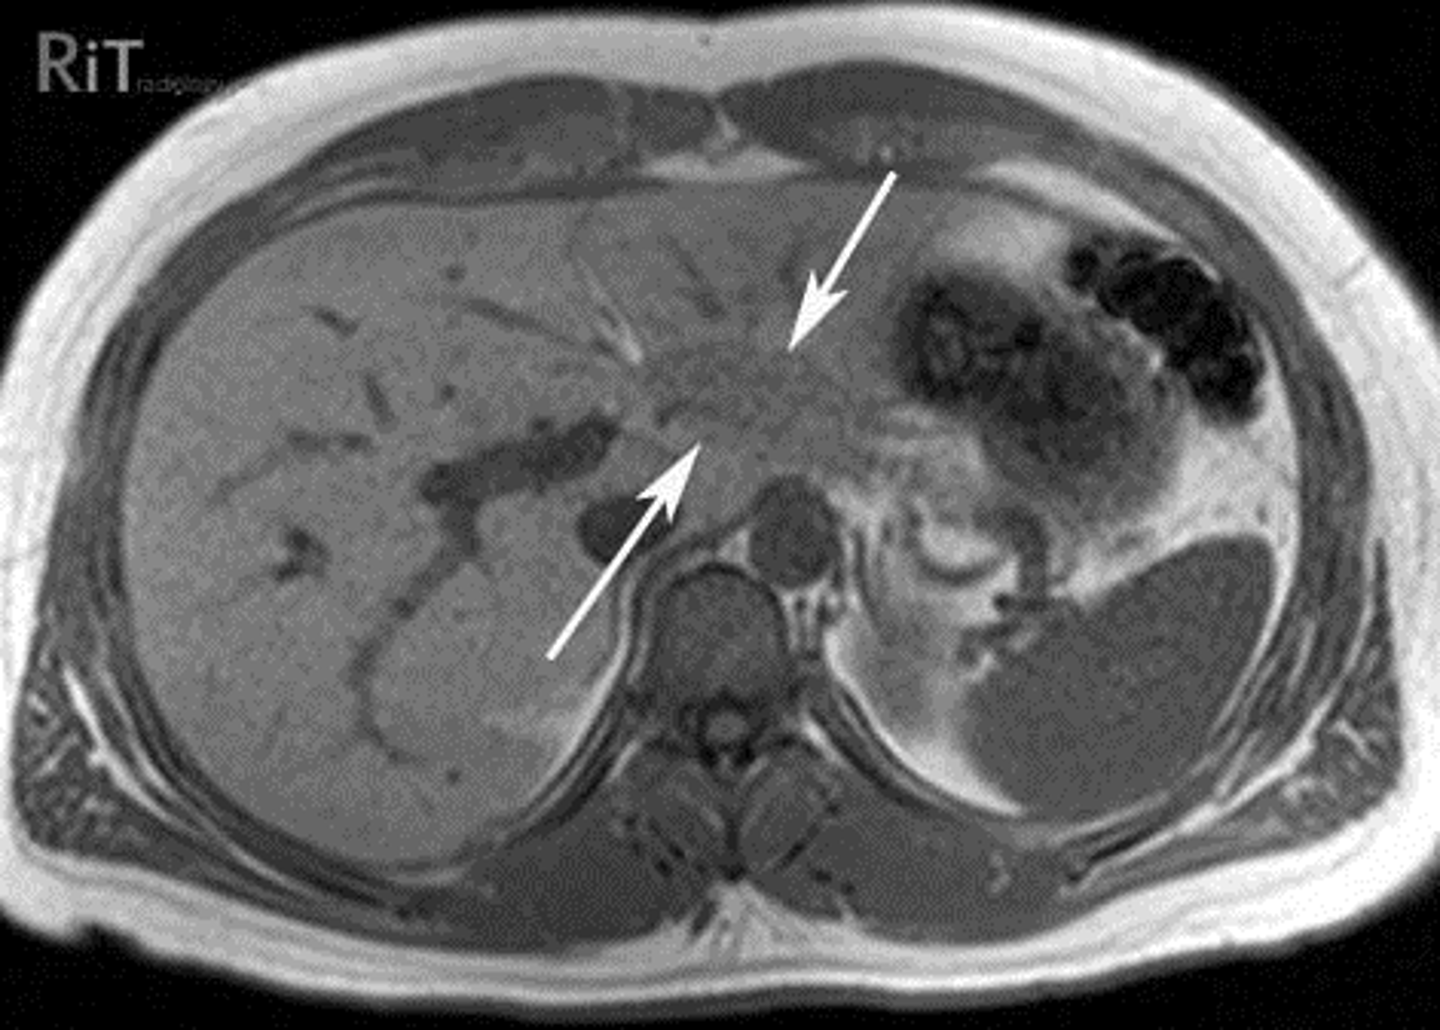

Normal Kidneys

K: Kidneys, lie in the renal fossae

DOTTED BLACK ARROWS: Central portion of the kidneys, should contain fat in a normal renal pelviz.

SOLID BLACK ARROW: Right renal artery, running posterior to the IVC

DOTTED WHITE ARROW: Left renal vein, lies anterior to the left renal artery.

SOLID WHITE ARROW: left renal artery.

A: Abdominal Aorta

IVC: inferior vena cava